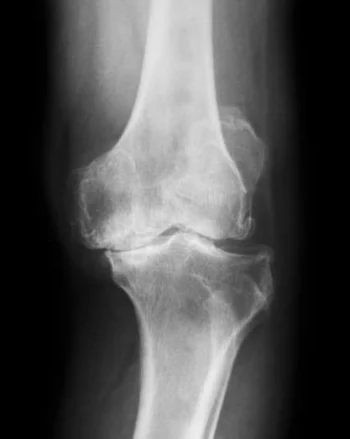

Gonartroza je najčešći razlog za ugradnju veštačkog kolena.

U 56% veštačko koleno dobijaju žene.

Drugi razlozi za atroplastiku kolena su npr.:

• reumatoidni artritis ii drugi oblici zapaljenskog artritisa

• teška povreda kostiju kolena

• hemofilija